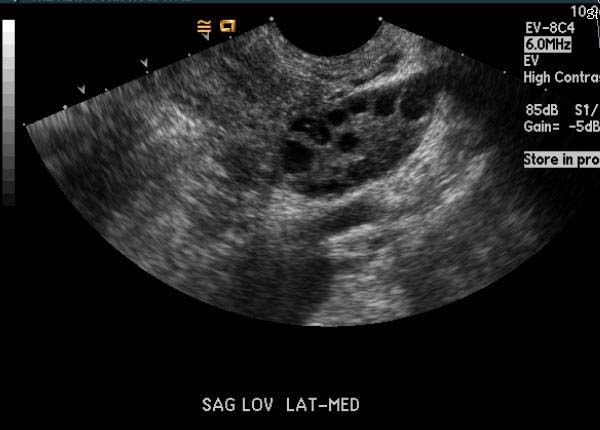

El ultrasonido obstétrico es uno de los estudios esenciales en el seguimiento prenatal, ya que permite visualizar el desarrollo fetal, estimar la edad gestacional, identificar posibles anomalías y monitorear el entorno uterino. Dada su importancia clínica, muchas mujeres embarazadas desean conocer cuál es su costo y en qué instituciones pueden realizarlo con seguridad y precisión diagnóstica.

Este estudio se puede realizar en hospitales generales, clínicas privadas, consultorios de ginecoobstetricia, centros de diagnóstico por imagen y laboratorios clínicos con área de ultrasonido. Es importante elegir una institución que cuente con personal capacitado, equipos modernos y un entorno adecuado para garantizar la seguridad y exactitud del procedimiento.

Además, se recomienda que el estudio sea solicitado e interpretado por un especialista en ginecología y obstetricia o en medicina materno-fetal, especialmente cuando se requiere evaluar estructuras anatómicas con mayor detalle.